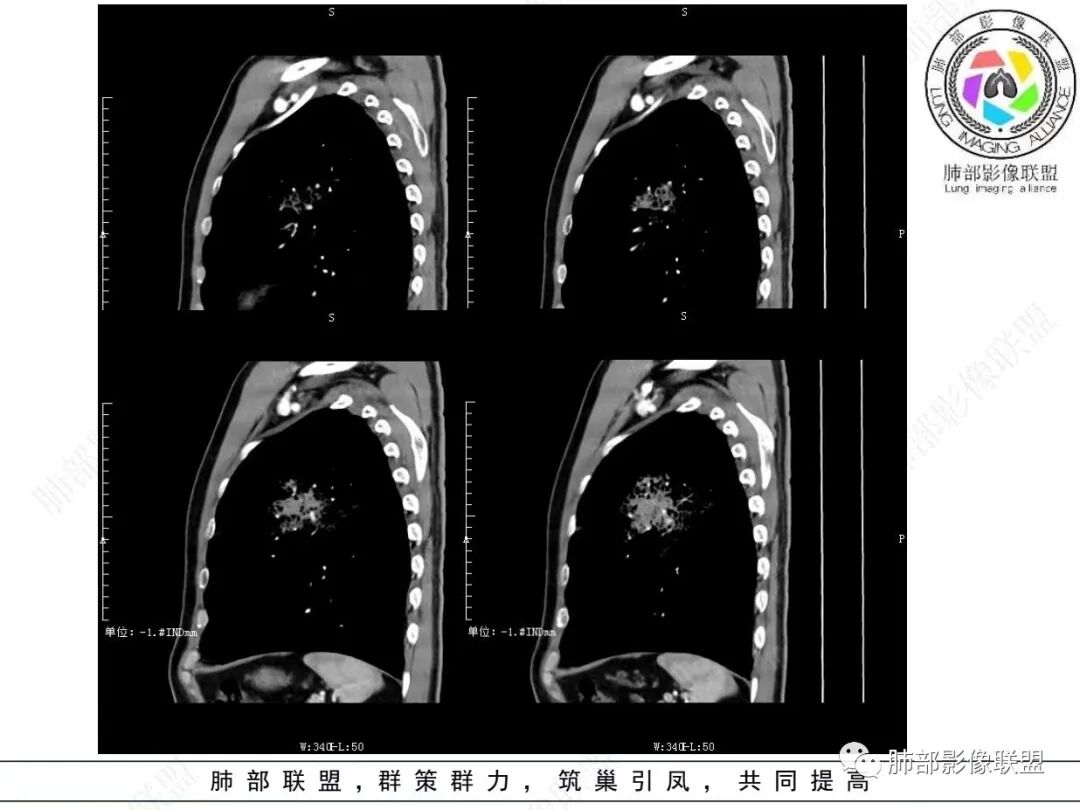

2.左肺上叶大片状混合密度影,未见空洞,实变影主要位于胸膜下,长轴与胸膜平行,实变区内部密度不均、其内可见多发小斑片状低密度影,磨玻璃影多位居肺门一侧,可见网格,磨玻璃影边界多可分辨,重力分布趋势。病灶区支气管显示较为通畅,进入外围实变区渐至消隐。病灶轻度不均匀低强化,病灶区肺动脉显示较良好,未见破坏。

双肺广泛分布微小磨玻璃密度结节影,腺泡结节样分布,密度大小较为均匀一致。